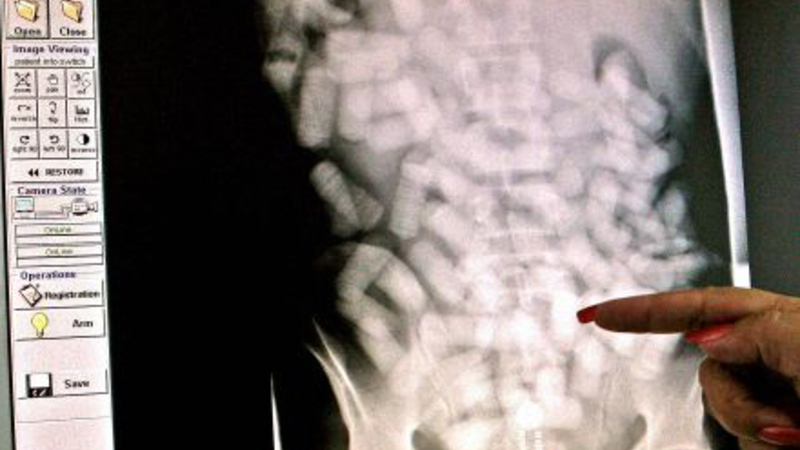

De sluger fra 500 gram og op til et kilo narko, mens én mand er taget med hele 1,233 kilo narko i organerne. Typisk smugles kokain, men også heroin finder vej til danske misbrugere i smuglernes maver.

Det er tydeligt at se poserne med narko på scanningsbilleder